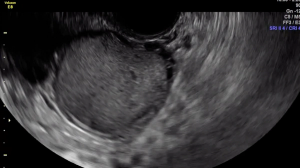

In this clip, fluid within the rectouterine pouch introduced following saline-infusion sonoPODography allows for appreciation of adhesions and a peritoneal pocket (enclosed fluid due to a defect in the peritoneum). These are two classic features of superficial endometriosis.

Although not clearly depicted in this clip, deep endometriosis likely is present posterior to the uterus at the level of the internal cervical os, as demonstrated by the irregular, hypoechoic area.